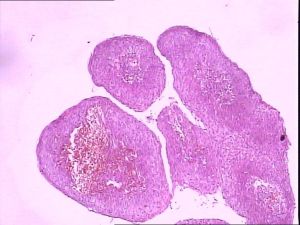

陰莖增生物臨床表現多種多樣,常在陰莖皮膚、憨膜部位出現多發件乳頭瘤樣或疣狀損害,最多見於冠狀溝、包皮、包皮系帶、尿道外口等處,也可見於陰莖體及周圍皮膚。初發時為單個或多個散在或密集成片的微小淡紅色丘疹,漸漸增大、增多,表面凹凸不平,濕潤而柔軟.呈現乳頭狀、指狀、菜花狀或雞冠狀,大小不等,淡紅色或污灰色。其根部常有蒂,易發生糜爛、滲液,觸之易出血,皮損裂隙中常有混濁的漿液或膿性分泌物,散發惡臭。伴瘙癢,常因搔抓而引起繼發細菌感染。

1、典型皮損為生殖器或肛周等潮濕部位出現丘疹,乳頭狀、菜花狀或雞冠狀肉質贅生物,表面粗糙角化。